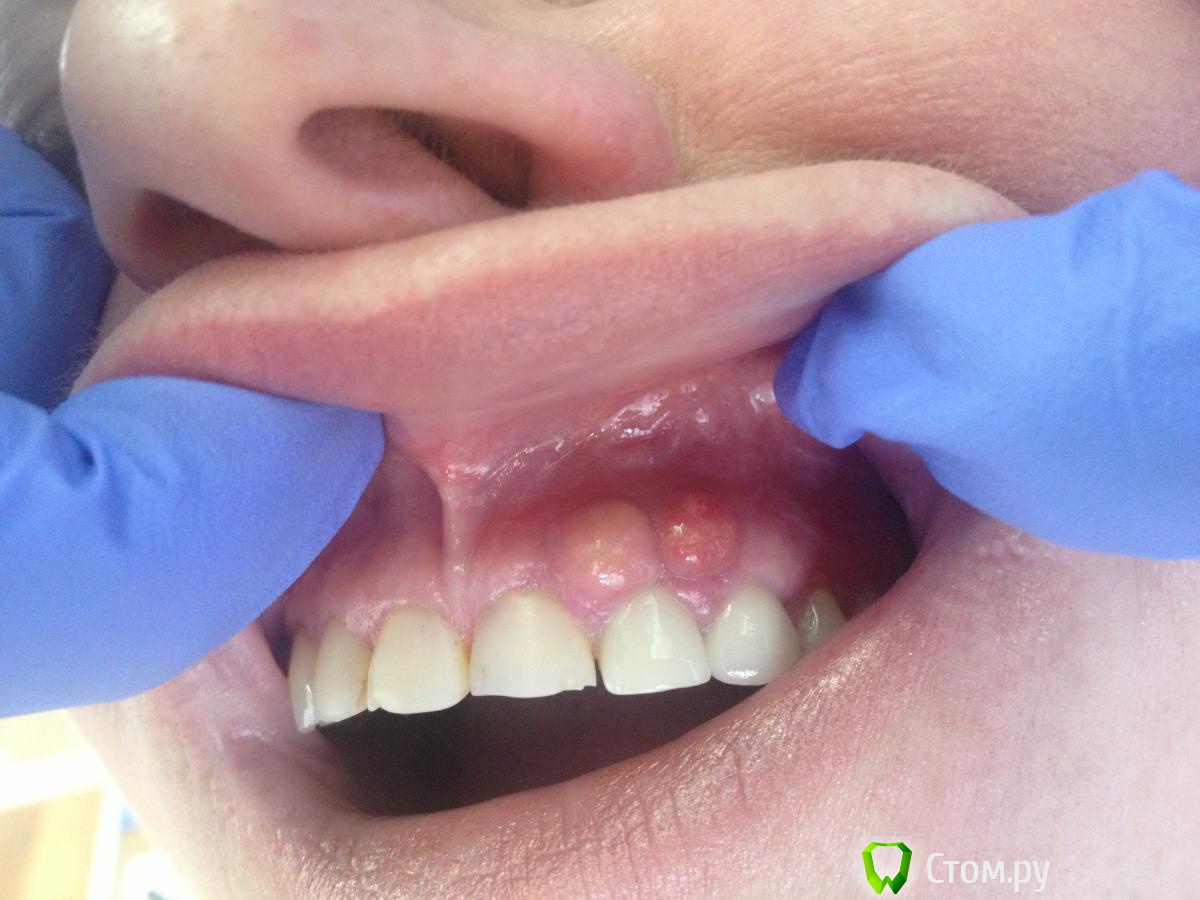

red_butler Опубликовано 27 февраля, 2014 Поделиться Опубликовано 27 февраля, 2014 Какие нибудь особенности есть при удалении таких разрастаний ?Если это эпулис - будет ростковая зона из периодонта, тщательно ее прокюретажить Ссылка на комментарий

kriokov Опубликовано 27 февраля, 2014 Поделиться Опубликовано 27 февраля, 2014 Какие нибудь особенности есть при удалении таких разрастаний ?может быть и пиогенная гранулема, если травма десны костью в анамнезе. Но по фотке не определишься.Будите иссекать-- не торопитесь до кости иссекать, уберите до надкостницы. Если только грануляционная ткань и следы гноя получите, то скорее всего пиогенная гранулема. Эсли эпулис- это как правило ростковая зона и иногда мелкий питающий сосуд. Тогда видимо всю толщу мягких тканей убирать придется, иногда с зубом. 1 Ссылка на комментарий

MaxDok Опубликовано 28 февраля, 2014 Автор Поделиться Опубликовано 28 февраля, 2014 При удалении получили гной . Ссылка на комментарий